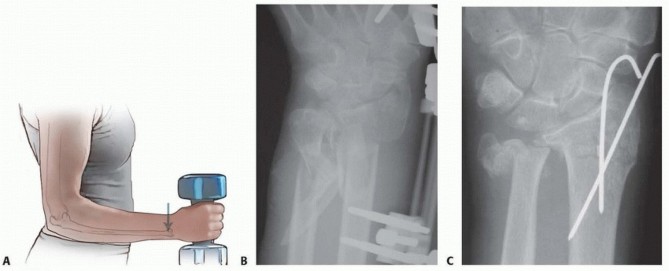

DEFINITION Distal radius malunion is best defined as malalignment associated with dysfunction. Malalignment d…

DEFINITION The distal ulna is the fixed point 7 around which the radius and the hand function ( FIG 1A ). Fra…

a DEFINITION Distal radius fractures occur at the distal end of the bone, originating in the metaphyseal regi…